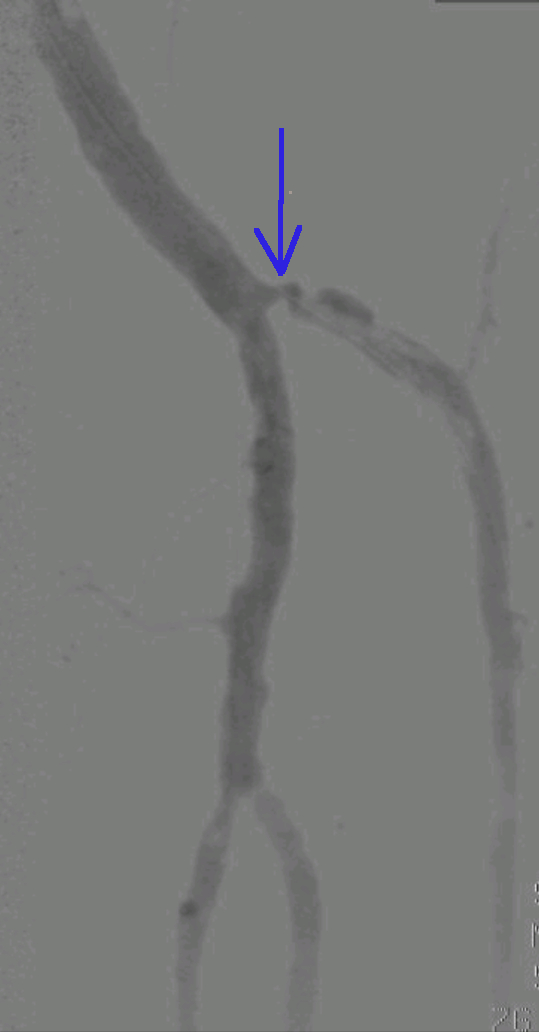

Žila arterija je prizadeta, zožena (modra puščica). Prekrvavitev noge je slaba. V primeru neukrepanja postane noga ogrožena. Noga dobi premalo kisika in premalo hrane.